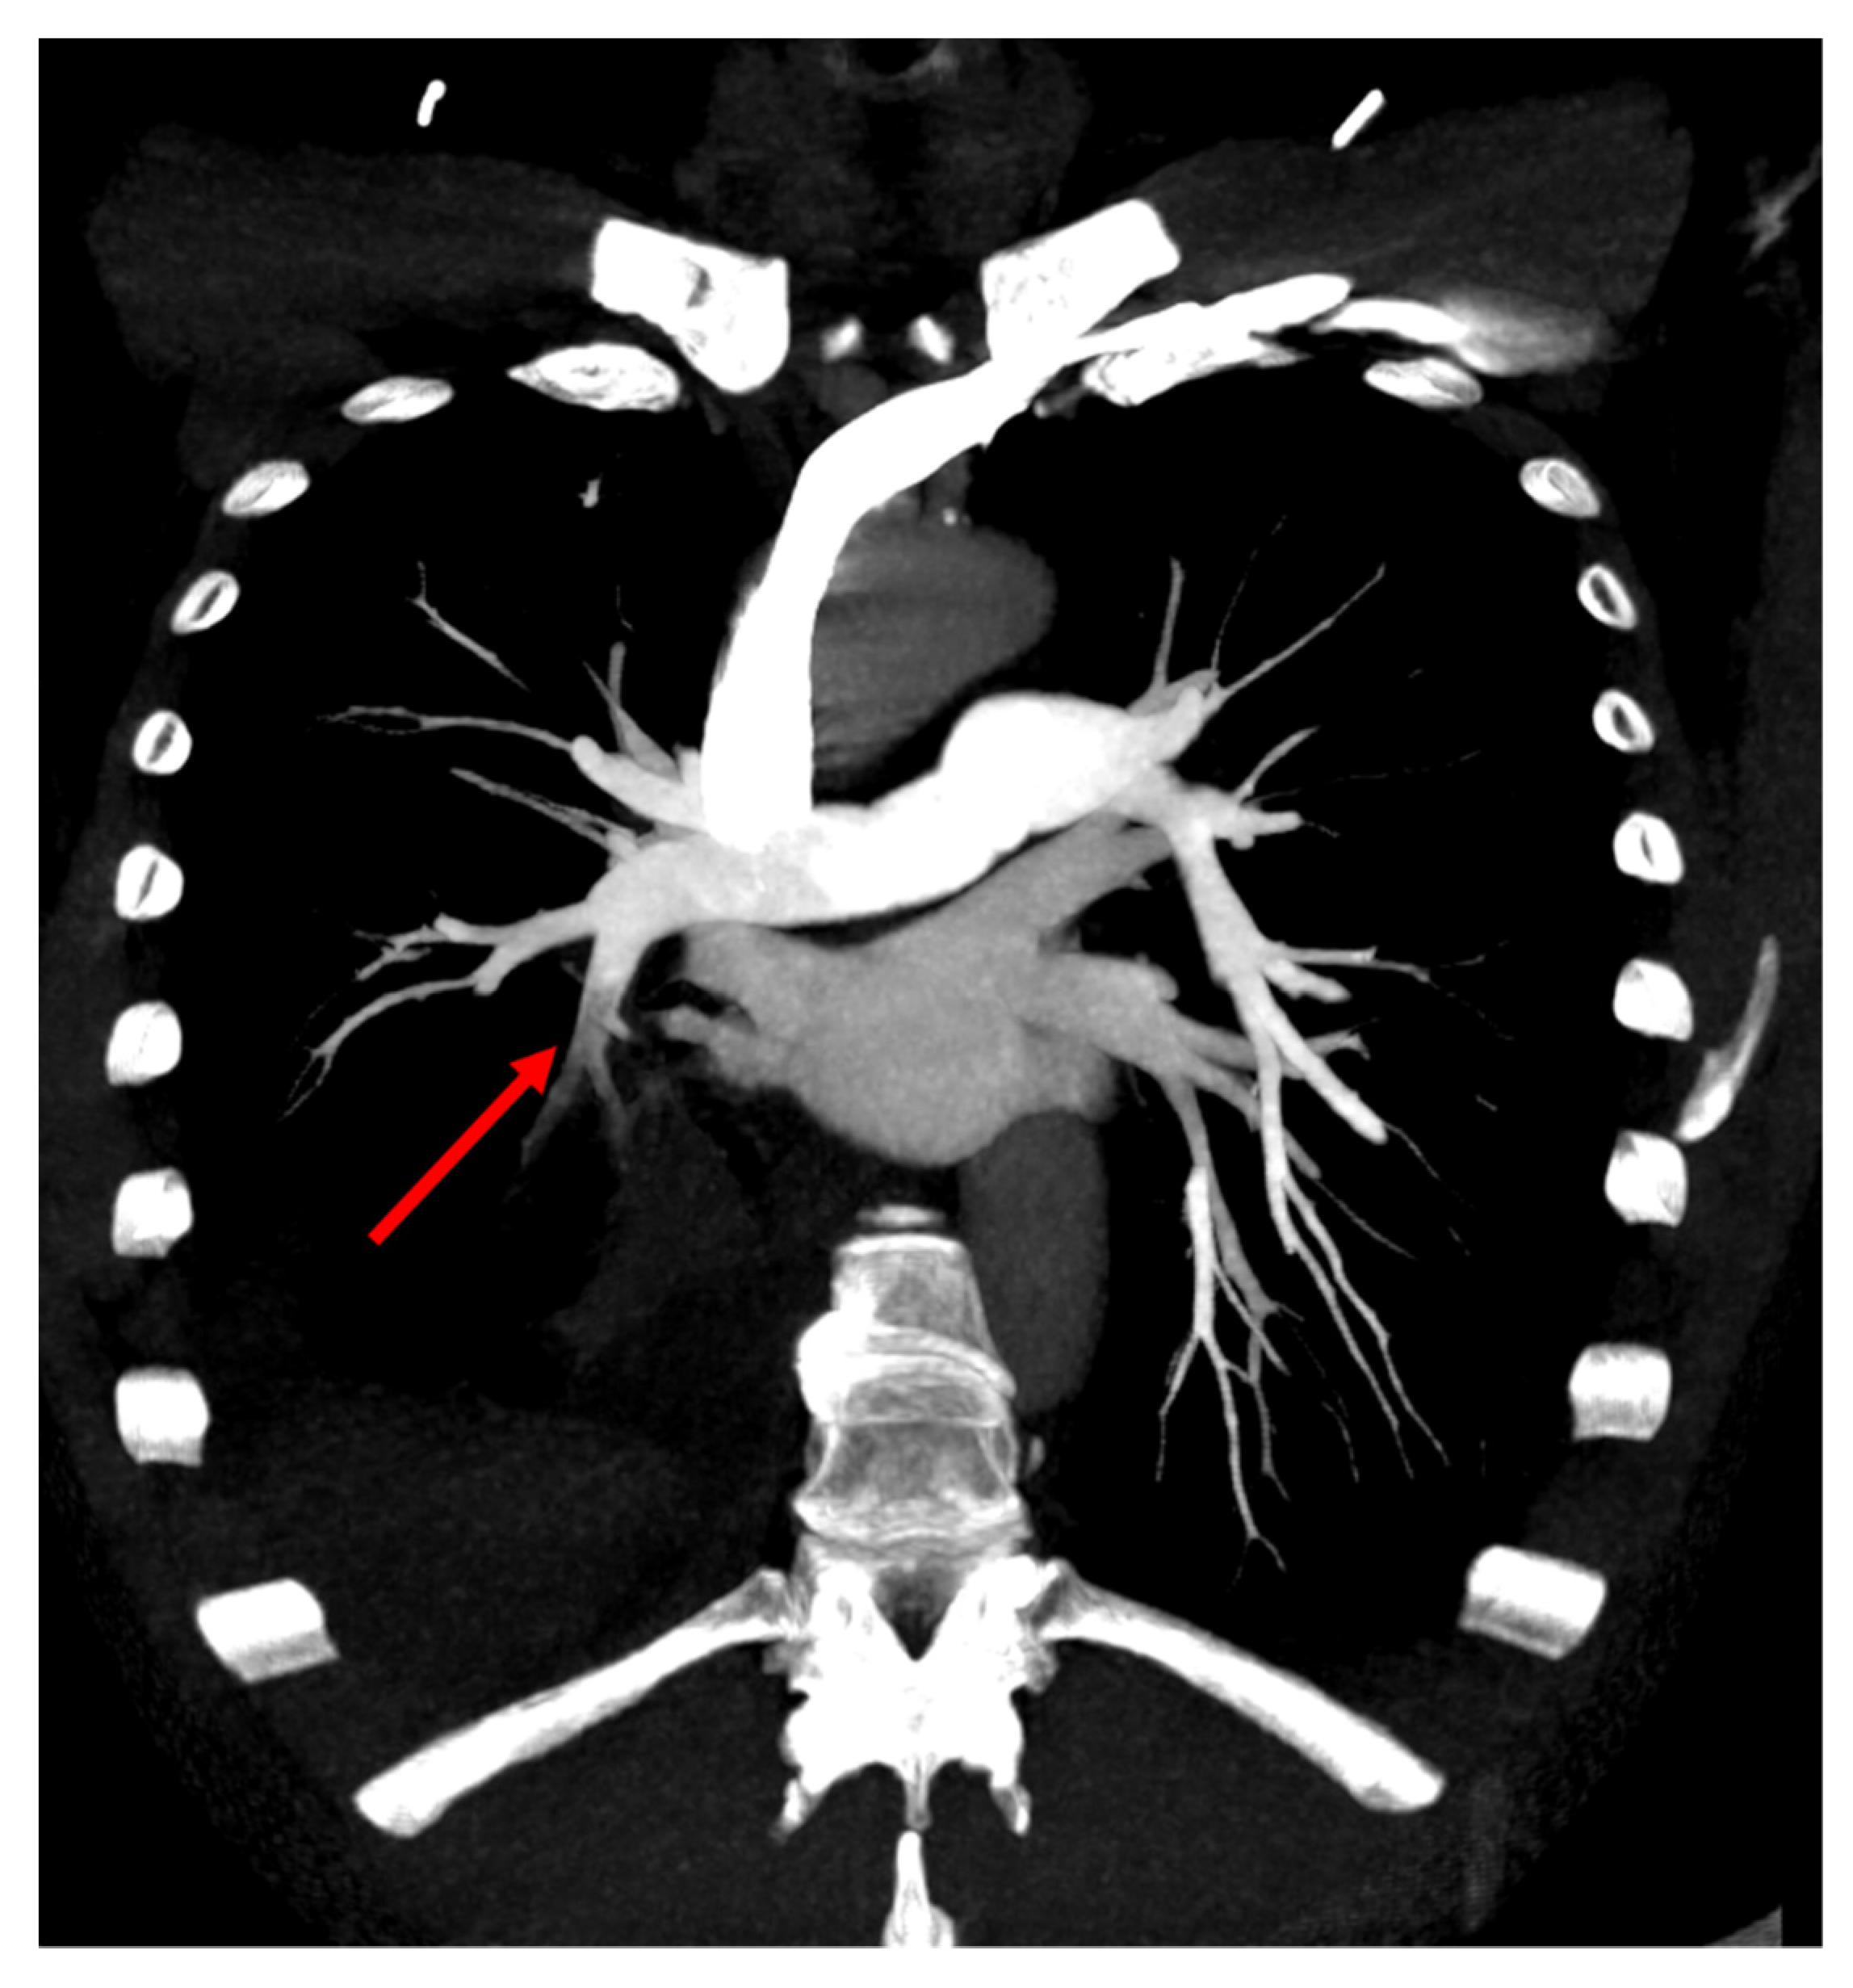

2. Case Presentation